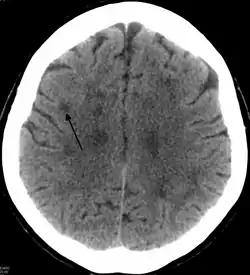

Neuroimaging

Standard MRI scans have been performed on 1.5 Tesla scanners with 5 mm thickness and 5 mm spacing to screen for white matter lesions in identified families. If signal intensities of the MRI scans are higher in white matter regions than in grey matter regions, the patient is considered to be at risk for HDLS, although a number of other disorders can also produce white matter changes and the findings are not diagnostic without genetic testing or pathologic confirmation.[2]